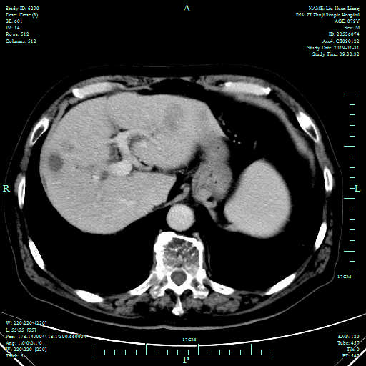

治疗期间定期复查CT评估病情(如下)

治疗2月后影像学比较:

2017.10.17MRI

2017.12.26CT

PR

之后2018.02.04、2018.04.24、2018.06.08定期复查上腹部CT增强,肝脏病灶对比(2017.12.26病灶相仿)。